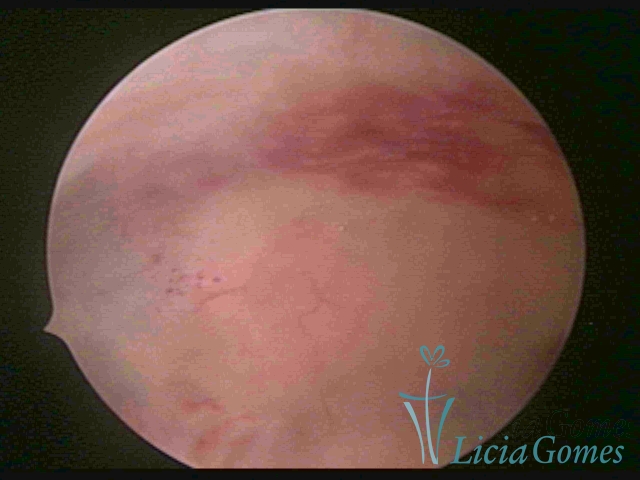

ENDOMETRITE CRÔNICA

A superfície do endométrio pode exibir alterações como um pontilhado vermelho formando novelos vasculares, o endométrio liso e hiper-vascularizado, ou com áreas vermelhas de forma intensa, com limites precisos e pontilhados branco amarelados no seu interior dando um aspecto “CASCA DE MORANGO” e uma coloração amarela pálida das comissuras fúndicas e laterais, em contraste com o vermelho intenso das paredes.